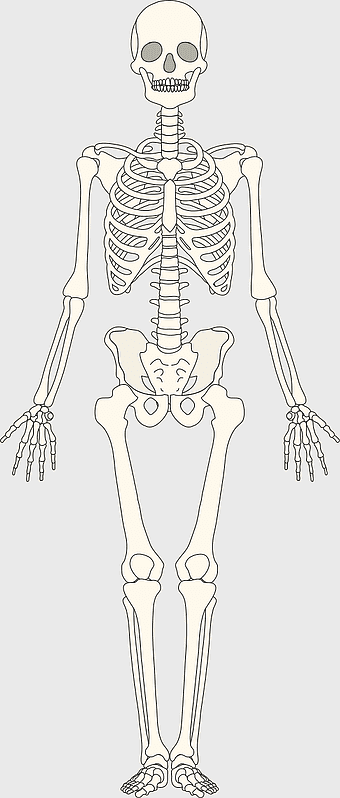

Human skeleton, rib cage anatomy, upper limb bones, joints in human body, skeletal structure analysis, vertebral column details, anatomical illustration study -

human skeleton illustration, skeletal system anatomy, axial skeleton structure, appendicular skeleton bones, human skeletal framework, skeletal joint connections, bone structure analysis -